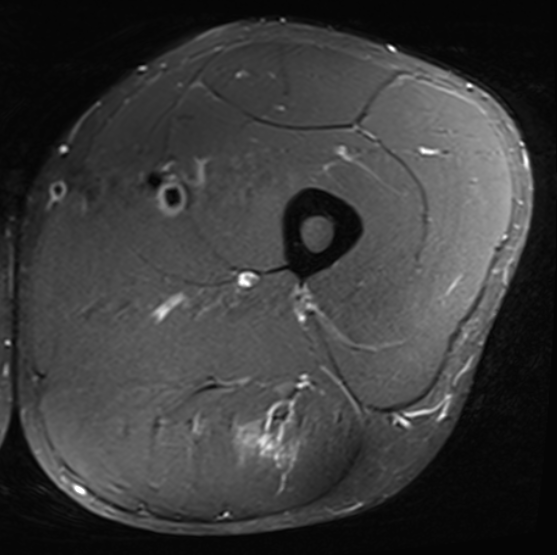

Grade 1A distal myofascial distal biceps femoris